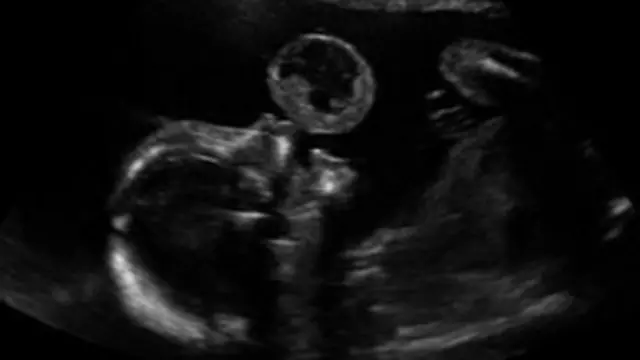

امریکہ میں ڈاکٹروں نے رحمِ مادر میں موجود پانچ ماہ کے ایک بچے کے منہ پر موجود ایک ٹیومر یعنی رسولی کا کامیاب آپریشن کیا ہے۔

ڈاکٹروں کا کہنا ہے کہ یہ ایک نایاب ٹیومر ہے جسے ’اورل ٹیراٹوما‘ کہتے ہیں ہے اور بہت کم توقع تھی کہ ان کی بچی زندہ رہ پاتی۔

رسولی نکالے جانے کے عمل میں حاملہ خاتون ٹیمی گونزالز کو لوکل انستھیزیا دیا گیا اور بچے کے گرد موجود حفاظتی غلاف کے اندر ایک سوئی داخل کی گئی۔ جس کے بعد لیزر کی مدد سے لِینا کے ہونٹوں پر موجود رسولی کو کاٹا گیا۔ یہ آپریشن ایک گھنٹہ تک جاری رہا۔